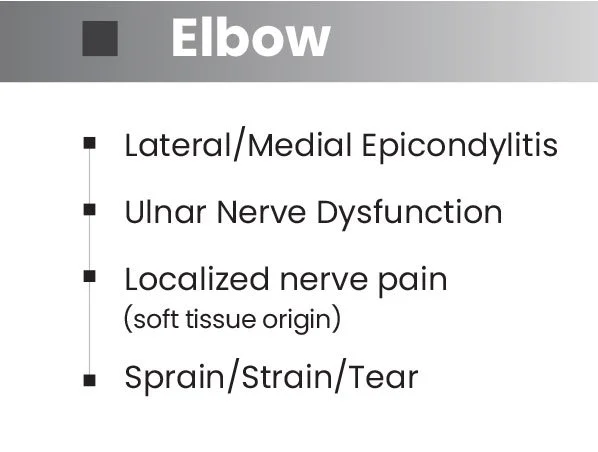

Effective Pain Reduction Across a Broad Range of Conditions.

Back, neck, shoulder, elbow and knee pain